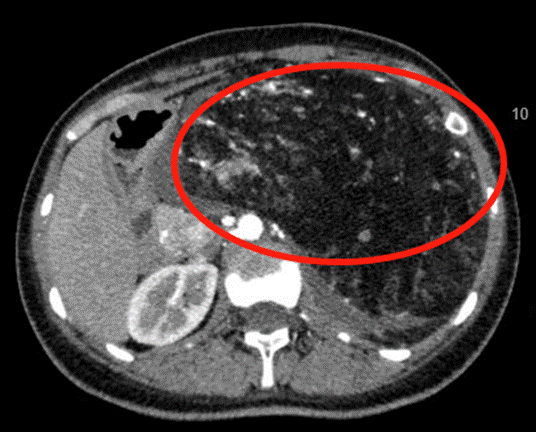

患者小潘因为反复出现进食后腹胀,去医院体检后却吓出了一身冷汗,腹部CT显示腹膜后32cm*16cm*10cm的巨大肿物,在多方打听后,慕名来到ac米兰官网中文网站一院群力院区普外科二病房,白雪巍教授在详细检查后发现,患者巨大的腹膜后肿瘤紧紧围裹住了腹主动脉、腹腔干、肠系膜上动脉,并且和肾脏相关联,解剖关系极为复杂。此时,如果冒险进行手术,很有可能损伤肾脏血管、输尿管,导致肾功能衰竭;甚至在剥离腹主动脉、腹腔干之时,术中突发不可逆转的大出血而致病人死亡。

“这个腹膜后肿瘤非常大,不仅大面积严重影响了消化功能,造成患者进食后腹胀,而且将肾脏推挤至肝脏下方,严重地影响生活质量,如果不能及时切除将造成多脏器功能障碍!”为确保手术安全,白雪巍教授与付宜鸣教授经过充分的术前评估与反复的讨论,及围手术期风险控制,术中出现各种并发症的应对措施。ICU、麻醉科、手术室及病房护理等科室均提前做好应急方案,确保做到患者手术安全最大化。最终成功地为患者根除6斤重的巨大肿物。